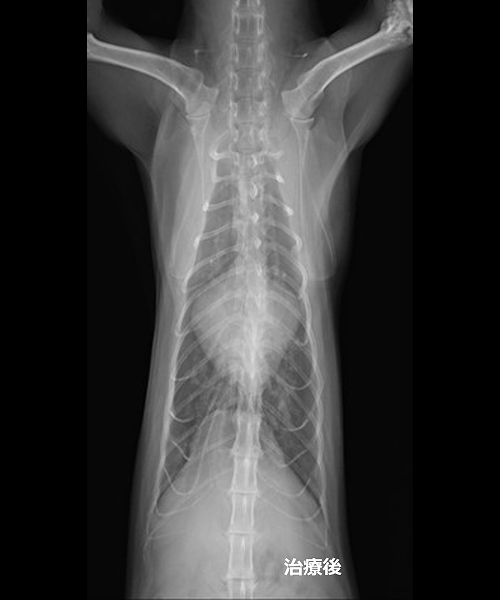

心臓外科手術後の胸部X線検査画像、心陰影が縮小していることがわかる

心不全の状態へ進行すると肺の中で血液が鬱滞し肺水腫となります。肺水腫になると酸素交換が上手く出来なくなるため酸欠状態となり、呼吸が荒くなったり舌の色が紫色になったります。

当院では、心臓超音波検査を行い治療薬を調整することで肺水腫になるリスクを軽減することができます。この弁膜症に対する治療は大きく分けて内科治療と外科治療があります。